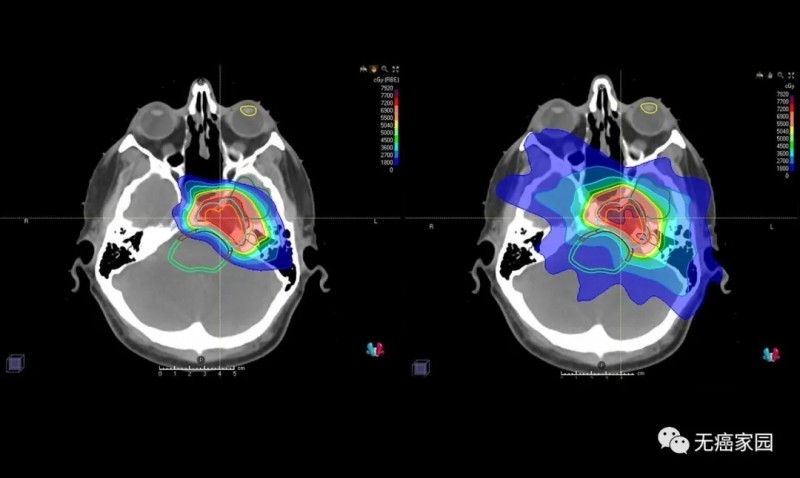

射波刀和质子刀比较,脑瘤射波刀和质子刀哪个好导读:近几年来,脑肿瘤的患病率是愈来愈高,脑瘤是神经外科中较为常见的疾病,针对人身心健康的伤害是十分大的,得了肿瘤是需要立即开展医治的。近几年来,脑肿瘤的患病率是愈来愈高,脑瘤是神经外科中较为常见的疾病,针对人身心健康的伤害是十分大的,得了肿瘤是需要立即开展医治的,要不然是会比较严重影响生活起居及其工作中,比较严重